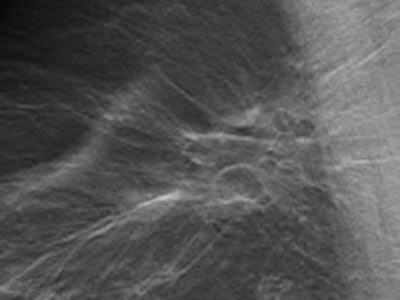

With tomosynthesis, low-dose images are obtained over a limited arc, and the projections are mathematically reconstructed into a series of sections with the hope that specificity and sensitivity will be improved. Initial work using tomosynthesis as an add-on to conventional 2D mammography suggested the potential for substantial improvements in specificity, the authors noted. They compared the diagnostic accuracy of 2D digital mammography with that of two-view (mediolateral and craniocaudal) and single-view (mediolateral oblique) tomosynthesis in an observer study involving two institutions: Cambridge and Capio St Göran's Hospital in Stockholm.

For diagnostic accuracy, 2D mammography performed significantly worse than two-view tomosynthesis (average area under receiver operating characteristic curve [AUC] = 0.772 for 2D, AUC = 0.851 for tomosynthesis; p = 0.021). The researchers found significant differences for masses and microcalcification (p = 0.037 and 0.049, respectively). The difference in AUC between the two modalities was significant only for the five readers with the least amount of experience (p = 0.03 versus p = 0.25 for readers with 10 or more years of experience). No significant difference was seen in reader performance when 2D mammography was compared with single-view tomosynthesis.